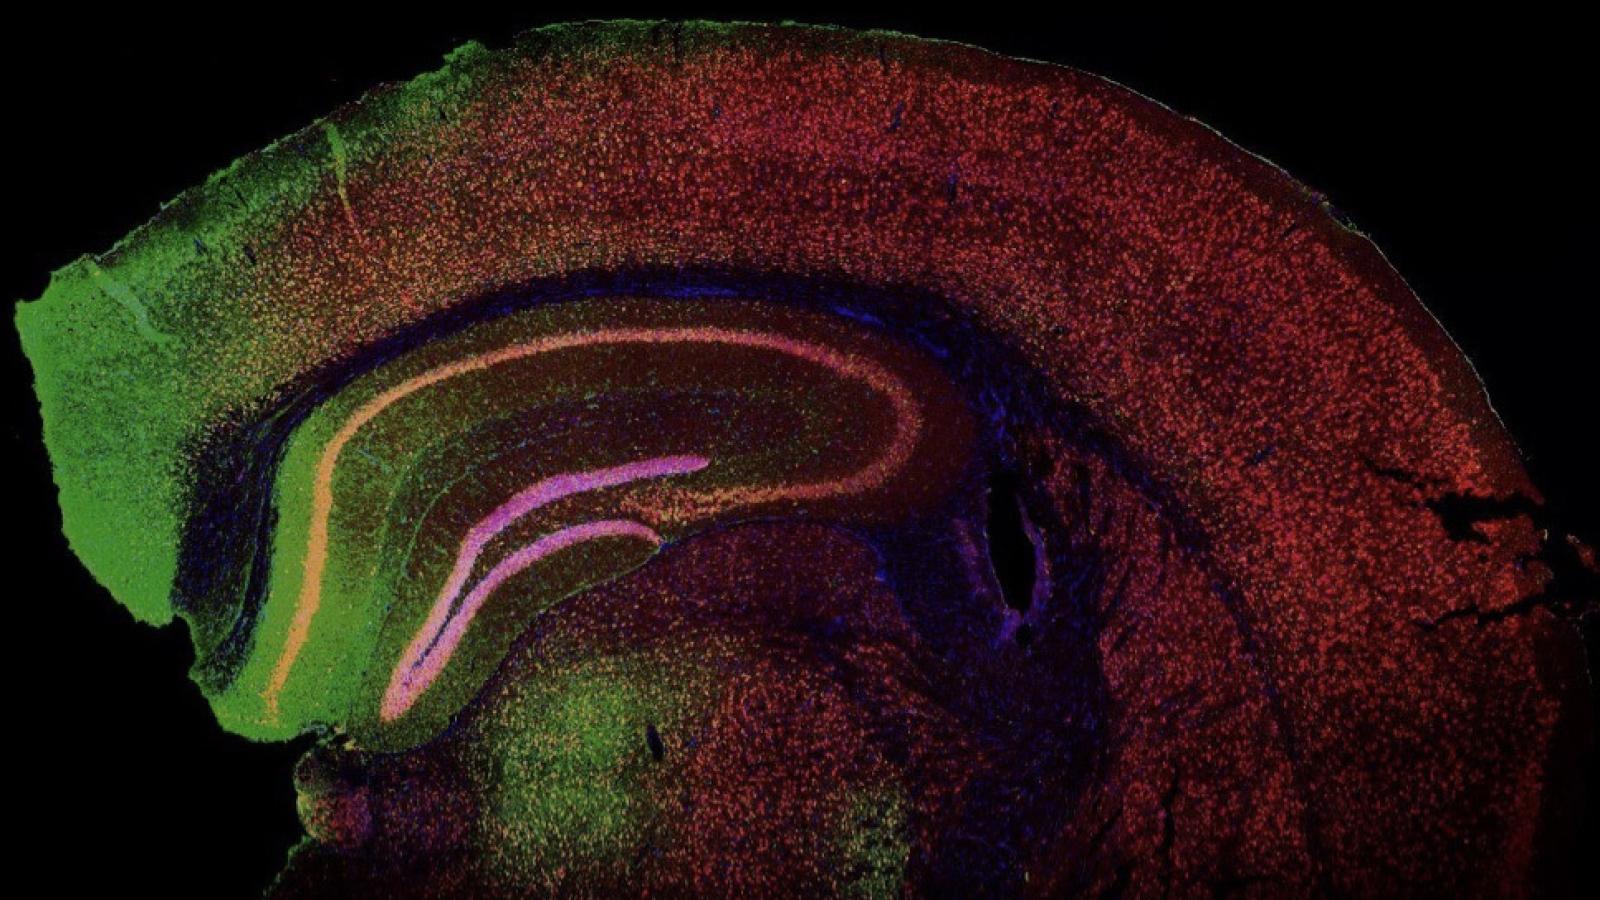

Banner image: Image of green fluorescent protein (GFP) expression in the mouse brain cortex following adeno-associated viral (AAV) vector injection. Courtesy of the Shaw Lab.